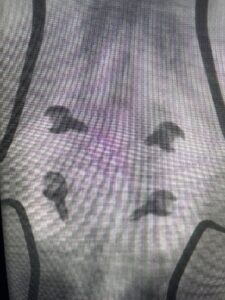

Another patient is a 62 year-old female with progressive low back pain and right leg pain and numbness that radiates to the top of her foot. She tried physical therapy and epidural injections. MRI demonstrated severe L3-4 stenosis and a grade 1 spondylolisthesis (Fig 4). There was L5-S1 and L4-5 disc collapse with modic end-plate changes. Biomechanically because of the significant degeneration of these disc spaces which stiffened the L4-S1 segment more stress was placed on the L3-4 segment, resulting in significant premature degeneration and compensatory stenosis and segmental instability. The MRI also showed pathologically, because of the slip, the L3 inferior processes were more anteriorly oriented and hence contributing to the majority of the lumbar canal compromise. Note the more sagittally-oriented facets in this case compared to the prior case (Fig 5). The patient underwent a decompressive laminectomy with attention of removing the inferior processes of L3 to fully decompress the canal. We also performed an L3-4 fusion with instrumentation (Fig 6). The patient had an uneventful postoperative course with improvement of leg pain. Of note with relief of the disabling leg pain patients are generally very happy. Patients can often manage their low back pain; it is the leg pain that they just can’t tolerate.

Fig 4: Sagittal T2-weighted lumbar MRI demonstrating L3-4 grade 1 spondylolisthesis with severe stenosis (blue arrow)